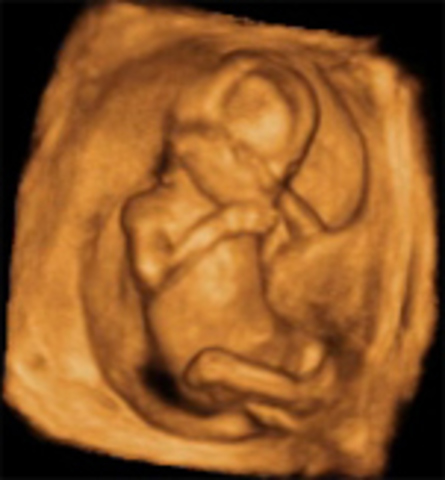

Semana 10

El embrión se denomina feto en lo sucesivo, la movilidad es mucho mayor e incluye movimientos corporales y de los 4 miembros; se mueve por todo el saco gestacional lleno de líquido amniótico. Las neuronas siguen multiplicándose de manera muy rápida. Los órganos esenciales del bebé ya se han formado y el feto se hace más resistente a las lesiones externas